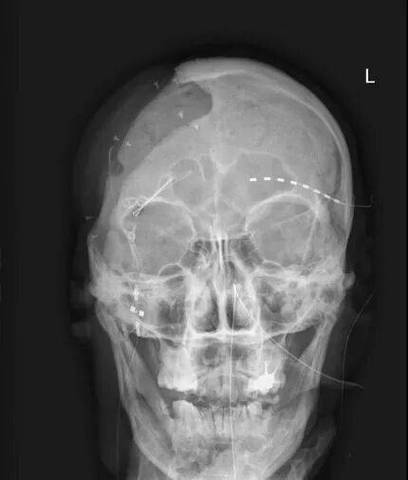

- 头颅左右两侧是否对称?下颌骨升支、髁突、颧弓等结构是否双侧对称显示?

- 头部倾斜(歪头): 导致正中矢状面不垂直,左右结构不对称,所有角度测量(如ANB角)和距离测量出现偏差。

- 头部前倾或后仰: 改变颅底平面(FH平面)与地面的关系,影响颅颌面结构相对位置的判断,导致ANB角、SN-MP角等测量错误。

- 眶点(Or)与耳点(Po)未水平对齐: FH平面倾斜,导致所有基于FH平面的测量(如下颌平面角、Y轴角)不准确。

- 鼻根点(N)未居中: 导致头颅影像在探测器上偏移,可能影响部分结构的显示和测量范围。